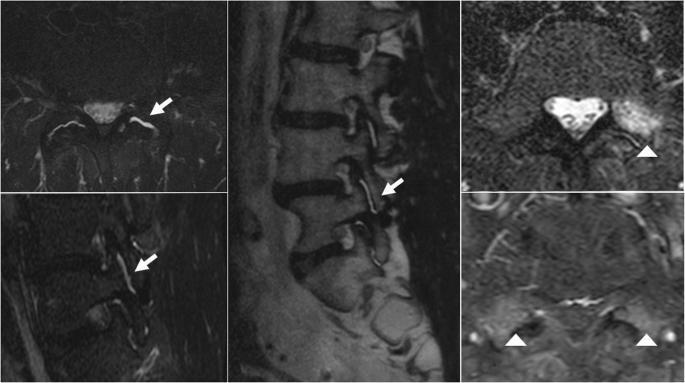

RMN DAS ARTICULAÇÕES FACETÁRIAS: INFLAMAÇÃO SINOVIAL ATIVA E EDEMA INTRA-ARTICULAR